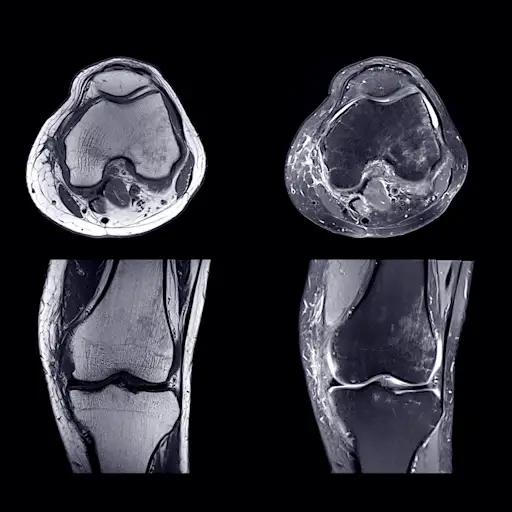

虽然风湿性关节炎被认为是一种关节疾病,但在超声或MRI上看到的第一个肌肉骨骼异常通常是肌腱,埃默里博士说。肌腱和韧带疼痛的发生是因为炎症过程(与损伤关节的过程相同)也会影响到结缔组织。如果你经常在没有明显解释的情况下肌肉或肌腱疼痛,最好去看医生,确定你的疼痛是与风湿性关节炎有关,还是其他原因,如过度使用损伤。